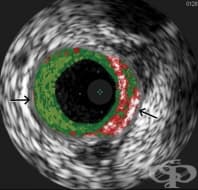

Интраваскуларен ултразвук е изследване, при което чрез миниатюрно ултразвуково устройство, прикрепен...